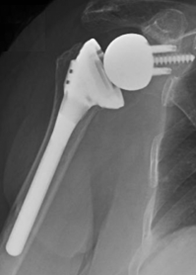

The reverse shoulder replacement can restore comfort and function to the arthritic shoulder with a massive rotator cuff tear, shoulder arthritis, or for failed conventional total shoulder replacement. When the rotator cuff is sufficiently torn that it no longer provides the necessary stability for the joint, the humeral head slides upwards. This results in slackening of the deltoid so that it can no longer raise the hand to carryout nor¬mal activities. The reverse shoulder provides stability of the shoulder joint so that the deltoid muscle can power the shoulder through a useful range of motion. In this procedure the arthritic ball is replaced by a socket fixed to the arm bone (humerus) by a stem that fits within it. A metal ball is fixed to the bone of the arthritic socket. Success requires technical excellence of the surgery and a commitment to a conservative rehabilitation program.

After a general or regional anesthetic, this procedure is performed through an incision between the deltoid and the pectoralis major muscles on the front of the shoulder. It in¬cludes release of adhesions and contractures and removal of bone spurs that may block range of motion. Our team of surgeons, anesthesiologists, and surgical assistants usu¬ally perform this procedure in less than two hours. The arthritic surface of the ball is replaced with a metal socket with a stem that is press fit down the inside of the arm bone (humerus) so that only the smooth surface extends from the bone. A metal ball is fixed to the bone of the arthritic socket.